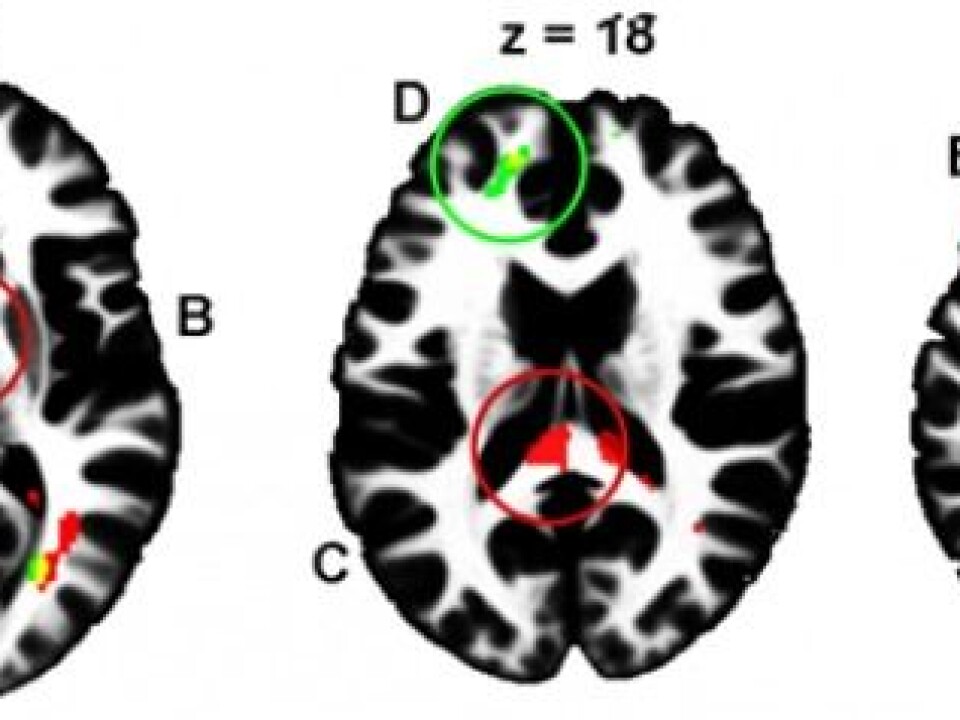

In fact, images taken of the brains of young men during the study reveal major differences in what is called "white matter". White matter constitutes the neural network, about 160,000 kilometres in length, that transmits signals in the form of nerve impulses and is crucial to the regulation of internal communication between the different areas of the brain.

Local differences in white matter are evident between high and low risk-takers as illustrated by the coloured areas adjacent to the prefrontal cortex, within interhemispheric tracts, and in the rear of the brain that controls vision. (Illustration: Sintef)

Images from brain scans revealed that those who made quick decisions and took chances during driving simulations had significantly more white matter than those who hesitated, evaluated the situation, and opted to drive safely.

Analysis of the white matter in the two groups also revealed major differences.